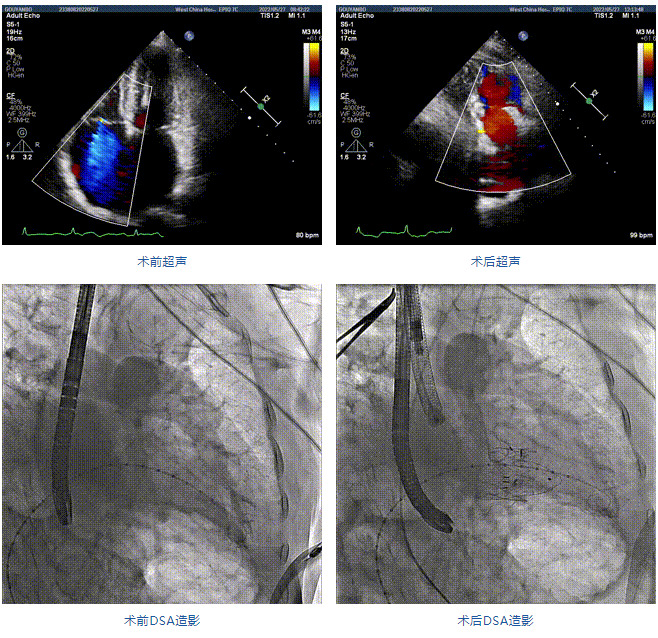

89歲男性。術前超聲報告顯示:雙房增大,左室壁肥厚,主、肺動脈增寬,三尖瓣重度反流。

團隊前期經過多次討論,制定了周密的手術策略和預案。由于患者已是近九旬的超高齡老人,傳統外科開胸手術風險極高,純介入經血管三尖瓣替換能夠明顯減少創傷。術中陳茂及馮沅教授結合體表定位在造影指示下精準穿刺右側頸靜脈并預置兩把血管縫合器。成功建立經皮血管入路后在食道超聲和DSA的引導下順利完成人工瓣膜植入,術后超聲和造影顯示人工三尖瓣同軸性良好,瓣架固定牢靠,無反流和瓣周漏,平均跨瓣壓差降為1mmHg。術畢收緊預置的血管縫合器縫線完成止血,縫合效果滿意,在手術室即刻拔除氣管插管。

陳茂教授:LuX-Valve Plus經血管三尖瓣置換系統可操作性強,植入效果好,創傷很小,有望成為治療重度三尖瓣反流患者的“有力武器”。本次手術的成功驗證了通過穿刺頸靜脈的純介入方式完成LuX-Valve Plus系統植入的可行性,也進一步驗證了通過該系統實施經導管三尖瓣置換的安全性和有效性,期待在后期臨床研究開展中使更多的三尖瓣反流患者獲益。